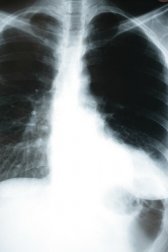

A pneumonia é uma infecção que afeta os alvéolos do pulmão. Estes são pequenos sacos cobertos por vasos sanguíneos nos quais ocorre o intercâmbio gasoso, ou seja, o oxigênio é captado do exterior e o dióxido de carbono (CO2) é eliminado. Por isso as consequências da pneumonia são tão importantes para o nosso organismo. Neste artigo, vamos explicar em detalhes como a pneumonia afeta o corpo humano.